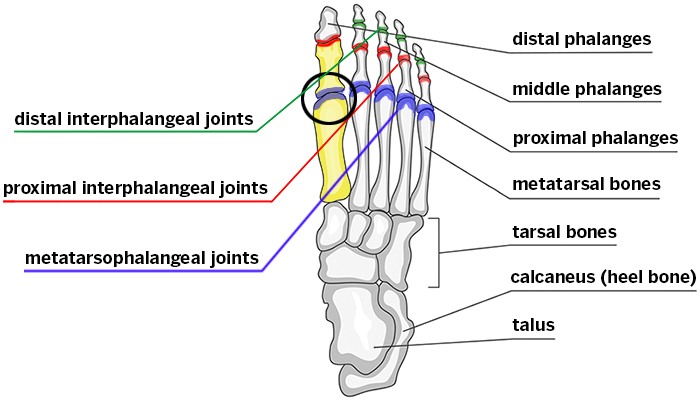

what are the bones of the foot?

metatarsals

phalanges

what do the metatarsals look like?

what are the landmarks of the metatarsals?

base

shaft

head

what is the styloid process of the 5th metatarsal?

insertion site for peroneus brevis

how are the phalanges of the foot based on?

distal

middle

proximal

what are the landmarks of the phalanges of the foot?

base

shaft

head

what do the phalanges of the foot look like?

what are the joints of the foot?

interphalangeal joints

(DIP, PIP)

metatarsophalangeal joints

intermetatarsal joints